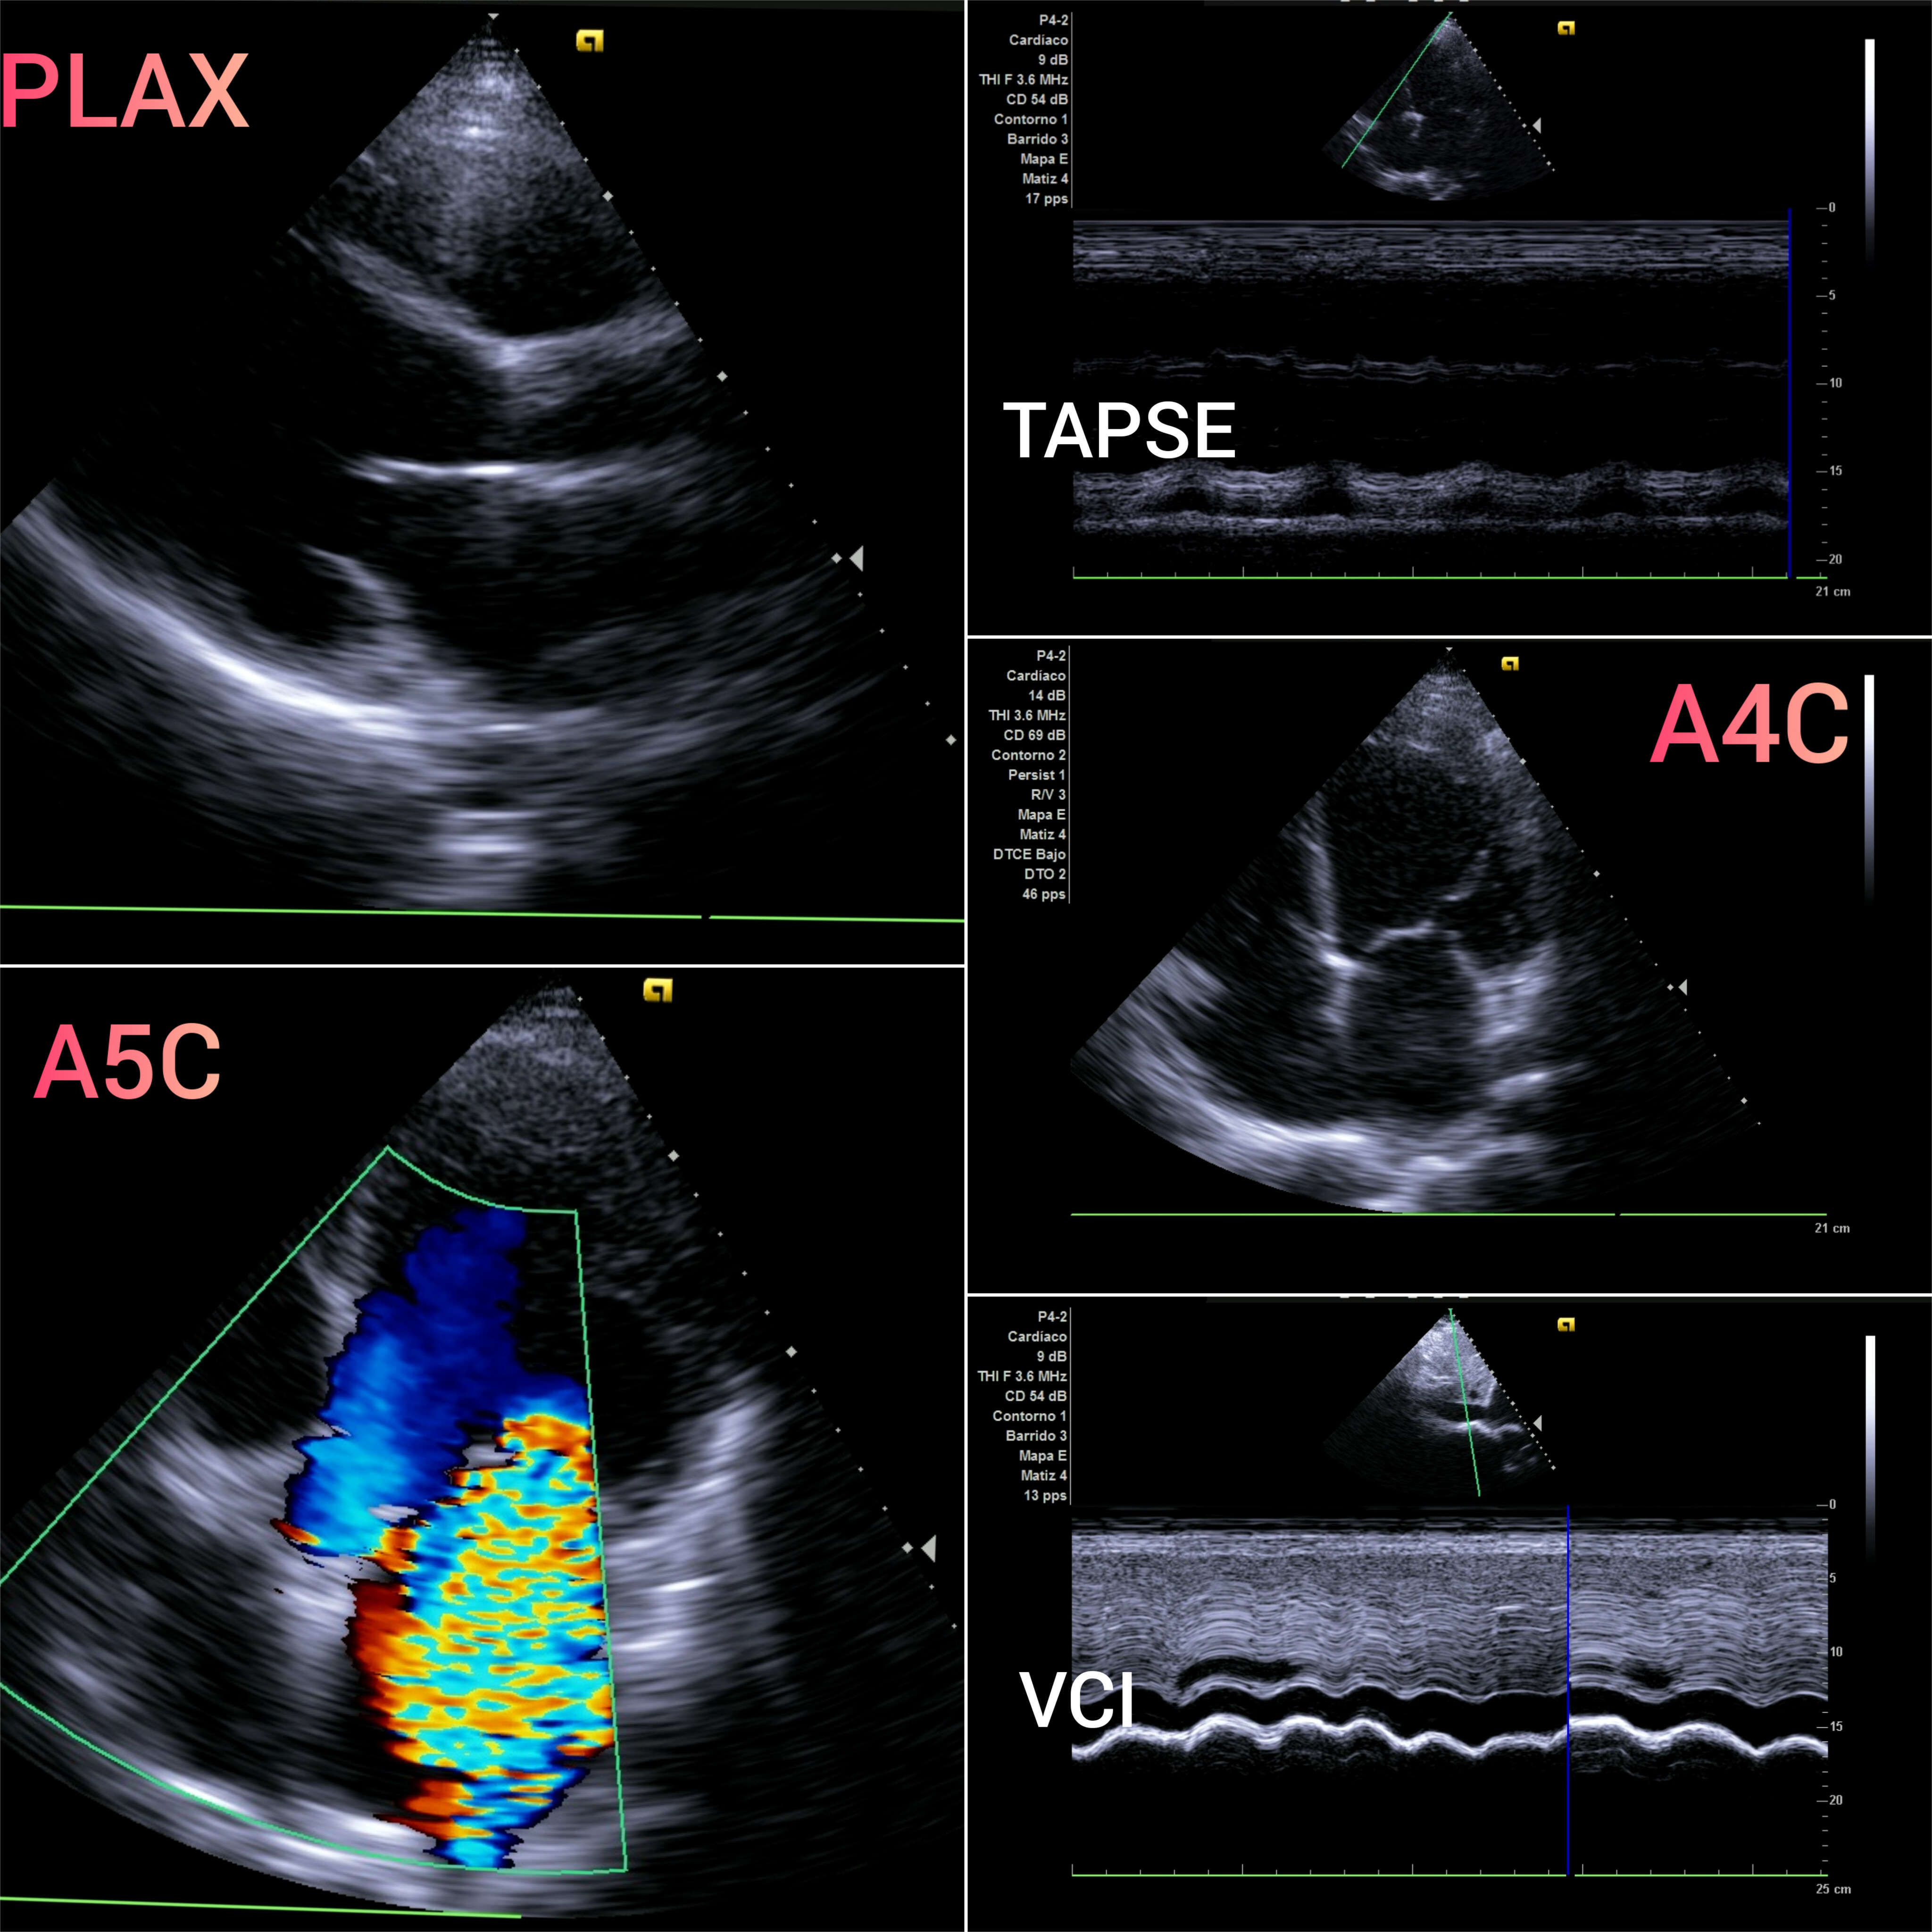

VEXUS: Vena cava inferior VCI 2,1 con colapsabilidad > 50%; Flujo portal y renal continuo.

EcoCardioscopia: Mejoría de contractilidad subjetivamente respecto a previo, cavidades izquierdas dilatatadas tanto VI como AI.